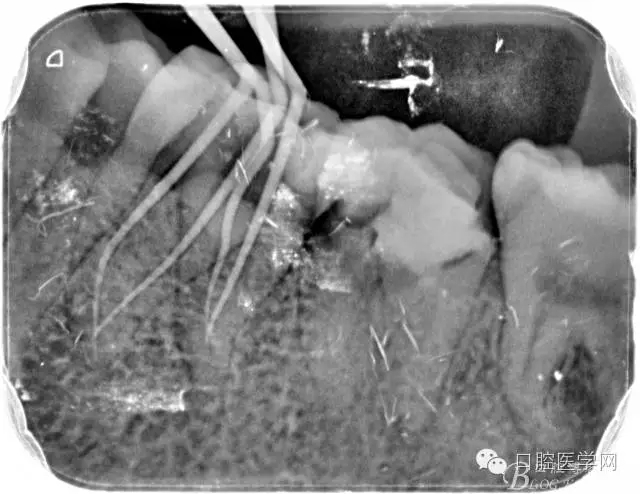

2、根管填充的界限

根管的解剖界限是从髓室根管入口到根尖部牙本质- 牙骨质交界处(生理性根尖孔) 。理想的根管充填应该是对生理性根尖孔冠方以上进行严密的三维封闭。临床上根据X线牙片判断根管充填的质量。牙片上充填材料与根管壁紧密接触一般被认为充填严密。关于充填止点,由于牙本质- 牙骨质界离根尖孔外表面平均距离为0. 5~0. 7 mm,同时相当多的根尖开口并不位于X线片的根尖处。因此临床上认为材料充填至距X线片牙根最尖端0. 5~1 mm (也有认为0. 5~2mm)为适填。